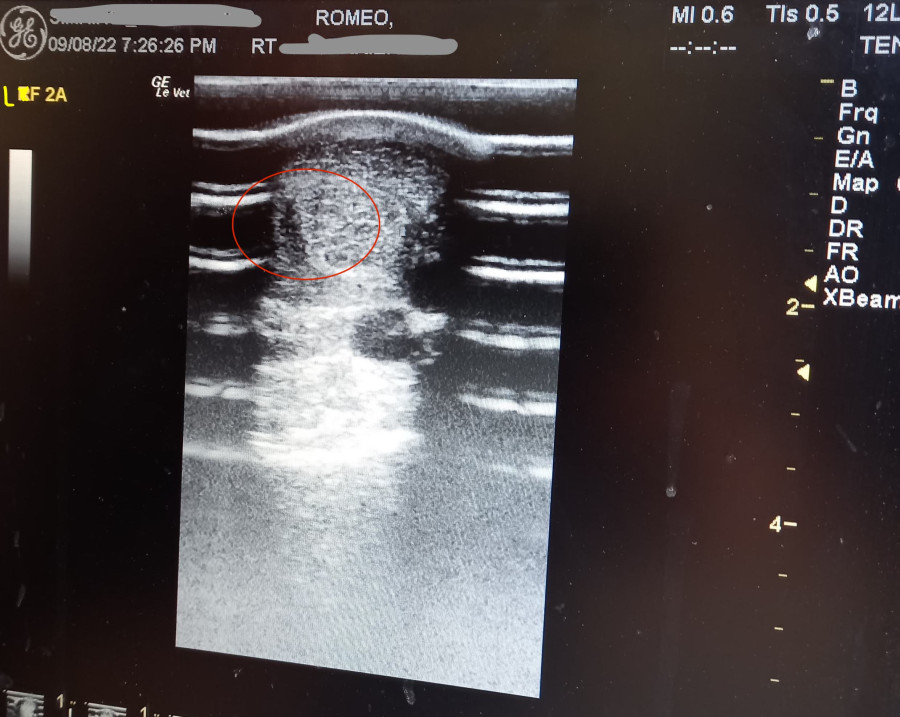

Le veto revient pour faire une echo, les trous sont bien présent sur les 2 posterieurs avec un ++ sur le Gauche.

Le printemps il retrouve un pré privé extérieur, puis il début Mai, nouvelle echo, cicatrisation à 90% il peut retourner avec les autres, on le rentre la nuit pour qu il se repose tout de même.

Juillet 2022, l Osteo passe il me confirme une bonne cicatrisation, je lui fait pars de mes doute car tendinite du flechisseur superficiel = tendinite des talons hauts... Donc pas de sens.